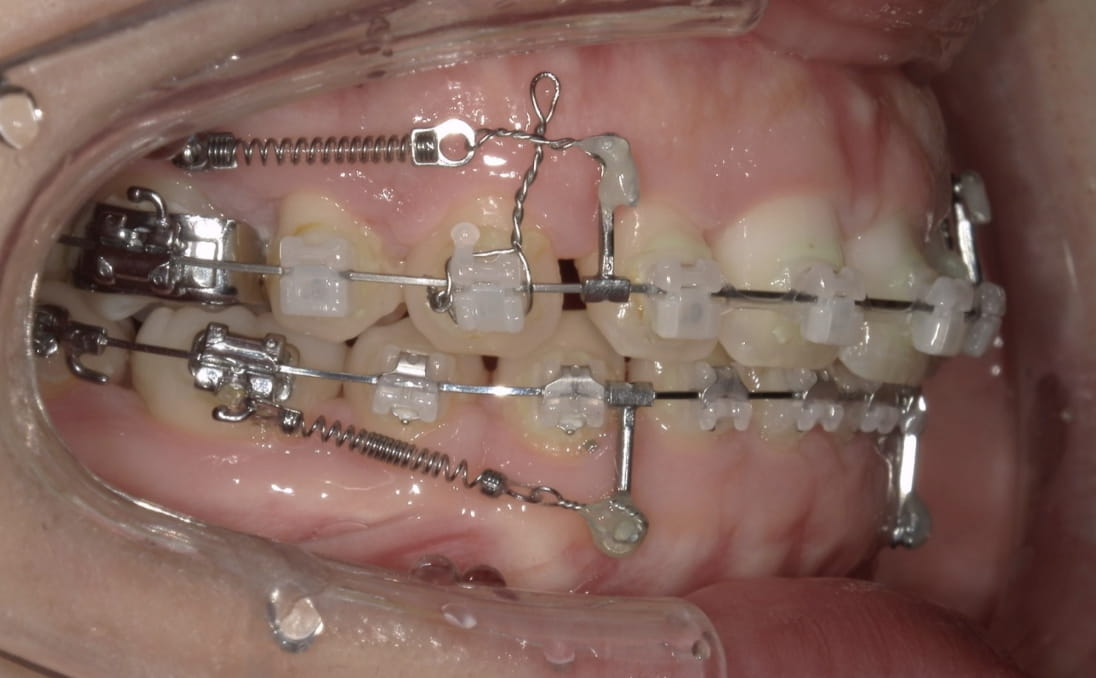

前歯を「倒す」のではなく「根元から平行に引く」技術

ここが最も重要なポイントです。前歯をただ内側に傾けるだけでは、歯が倒れて不自然な口元になります。インプラントアンカーにフックを取り付けて引っ張る、またはワイヤーにループメカニクスを組み込むことで、歯を根元から平行に後退させる歯体移動(リトラクション)が実現します。%集中できます。骨格的な突出でも、アンカーがあれば最大限まで改善できます。

前歯の「根元」と「先端」に均等に力を加えることで傾かずに平行移動します。

これが、マウスピース矯正では難しく、ワイヤー矯正が口ゴボ治療に有利な最大の理由です。

アンカー+フック牽引

アンカーにフックを掛けて前歯を平行に牽引(岡本さん・1年半後)

ループメカニクス

ワイヤーにループを組み込んで前歯を根元から平行移動(辻井さん・治療中)